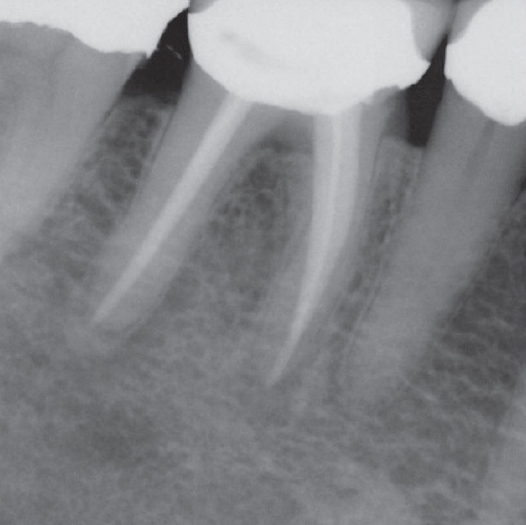

After

After Root Canal treatment